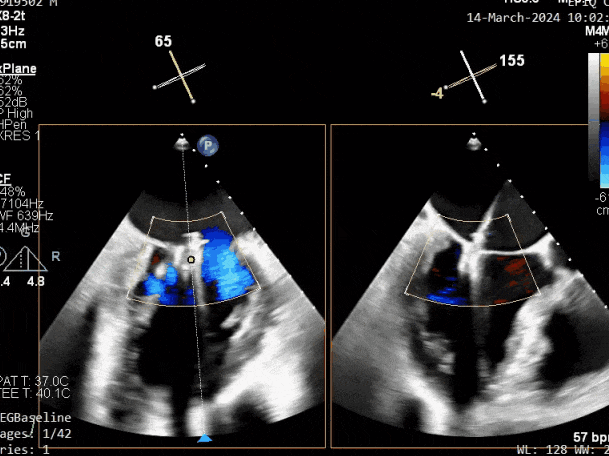

第二个瓣膜夹释放前评估,二尖瓣反流减轻

第二个瓣膜夹释放前评估,二尖瓣平均跨瓣压差及瓣口面积

第二个瓣膜夹释放后评估,二尖瓣呈双孔,外侧仍有残余反流

第三个瓣膜夹释放后评估,释放后评估,二尖瓣呈双孔,组织桥张力合适,瓣膜夹轴向与二尖瓣闭合线垂直,无残余反流

肺静脉血流频谱恢复为收缩期正向